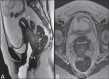

Magnetic resonance imaging is a method with high contrast resolution widely used in the assessment of pelvic gynecological diseases. However, the potential of such method to diagnose vaginal lesions is still underestimated, probably due to the scarce literature approaching the theme, the poor familiarity of radiologists with vaginal diseases, some of them relatively rare, and to the many peculiarities involved in the assessment of the vagina. Thus, the authors illustrate the role of magnetic resonance imaging in the evaluation of vaginal diseases and the main relevant findings to be considered in the clinical decision making process.